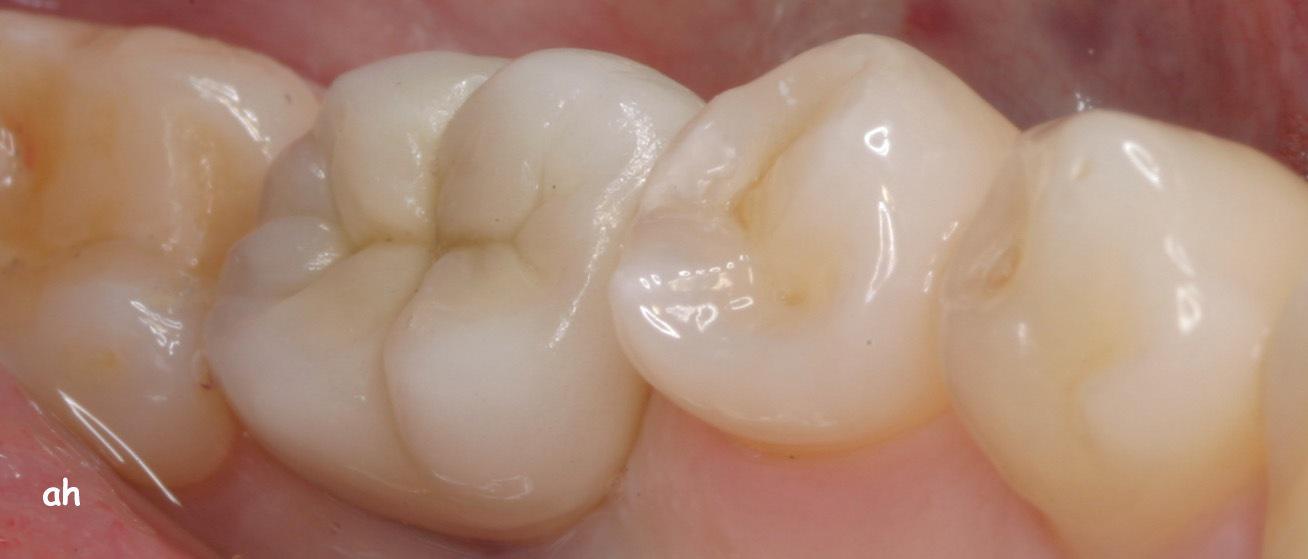

Exemple 5: Un implant au niveau d'une molaire inférieure gauche.

Exemple 5: Le moignon en titane est vissé sur l'implant.

Exemple 5: La couronne céramique est réalisée au laboratoire.